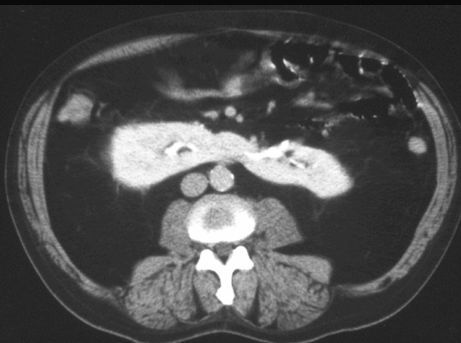

NERKA PODKOWIASTA

TK